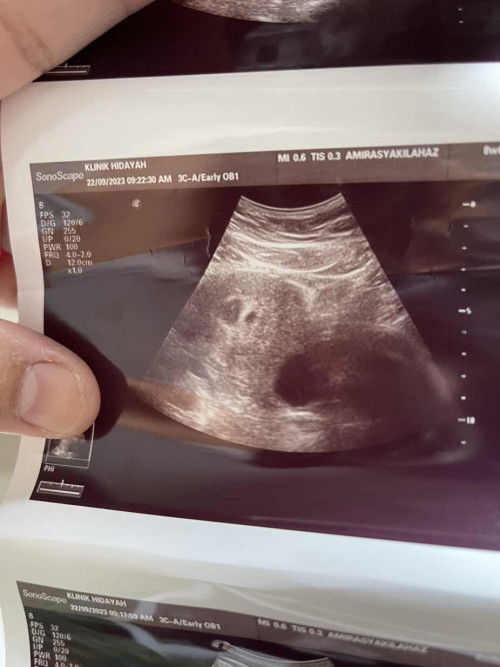

saya missed miscarrage utk kali kedua selepas jarak lebih kurang 3 bln lepas... pastu lekat balik tp missed miscarrage lg sedih yg teramat sgt😭 sbb 1st scan doc ckp nampak 2 kantung kelmarin sy excited utk repeat scan nk tgk progression tp lain plk jadi nya nmpk kntung shaja yg spatutnya bleh nmpak bntuk baby sbb sy dah 11/52 harini😢 dan ade bleeding jgk...skrg tggu lg 2 mggu kalu xtrun darah semua utk buat dnc😔 #ttc2ndchild

missed miscarriage/kehamilan kosong..sy sedang mengalami utk kehamilan kedua sy...harini genap 12 mggu spatutnya kehamilan sy...semasa 9mggu sy pergi scan utk comfirmkan pregnent tp scan masa tu just nampak kantung shj yg spatutnya dah boleh nampak heart beat then doctor sruh sy repeat scan after 2mggu...sy pon repeat la and sedihnya kantung pon nmpak mcm dah leper ...cek upt naik 2 line tp samar2...tp sebarang tanda miscarriage xde mcm bleeding tp sakit badan lenguh2 tubuh shj...then doctor sruh sy monitor dlm masa 2mggu sebarang pendarahan yg keluar....sy redha tiada rezeki utk kalini...mgkin belum masanya yg sesuai Allah nak bg sy utk timang ank kedua...kalau sapa2 ade pengalaman mcm sy boleh share dekat sini ye... skrg sy tgh risau...sy takut period sy x kembali normal mcm sebelum ni...#missedmiscarriage